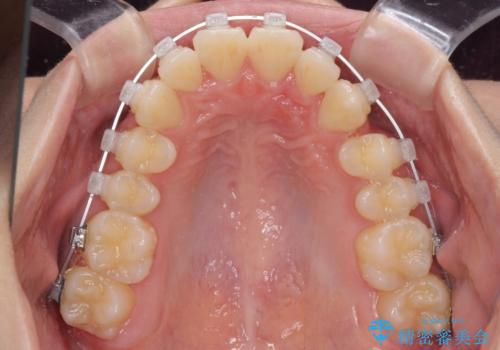

ぱっと見はインビザラインによる矯正治療も可能と思われましたが、歯根が最も長い犬歯がクロスバイトになっており、インビザラインでは対応困難と判断され、ワイヤー装置にて矯正治療を行うこととしました。

クロスバイトになっている犬歯は、歯の移動に伴い装置を張り替えていくことで対応することとしました。

クロスバイト改善中には歯髄壊死を起こすリスクがあるため、神経に問題がないか確認しながら治療を進めて行く必要があります。

思っていたよりも早くクロスバイトは改善され、歯髄壊死に至ることなく、無事に治療を終えることができました。